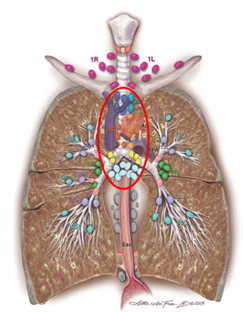

肺癌淋巴结图谱.ppt_第3页